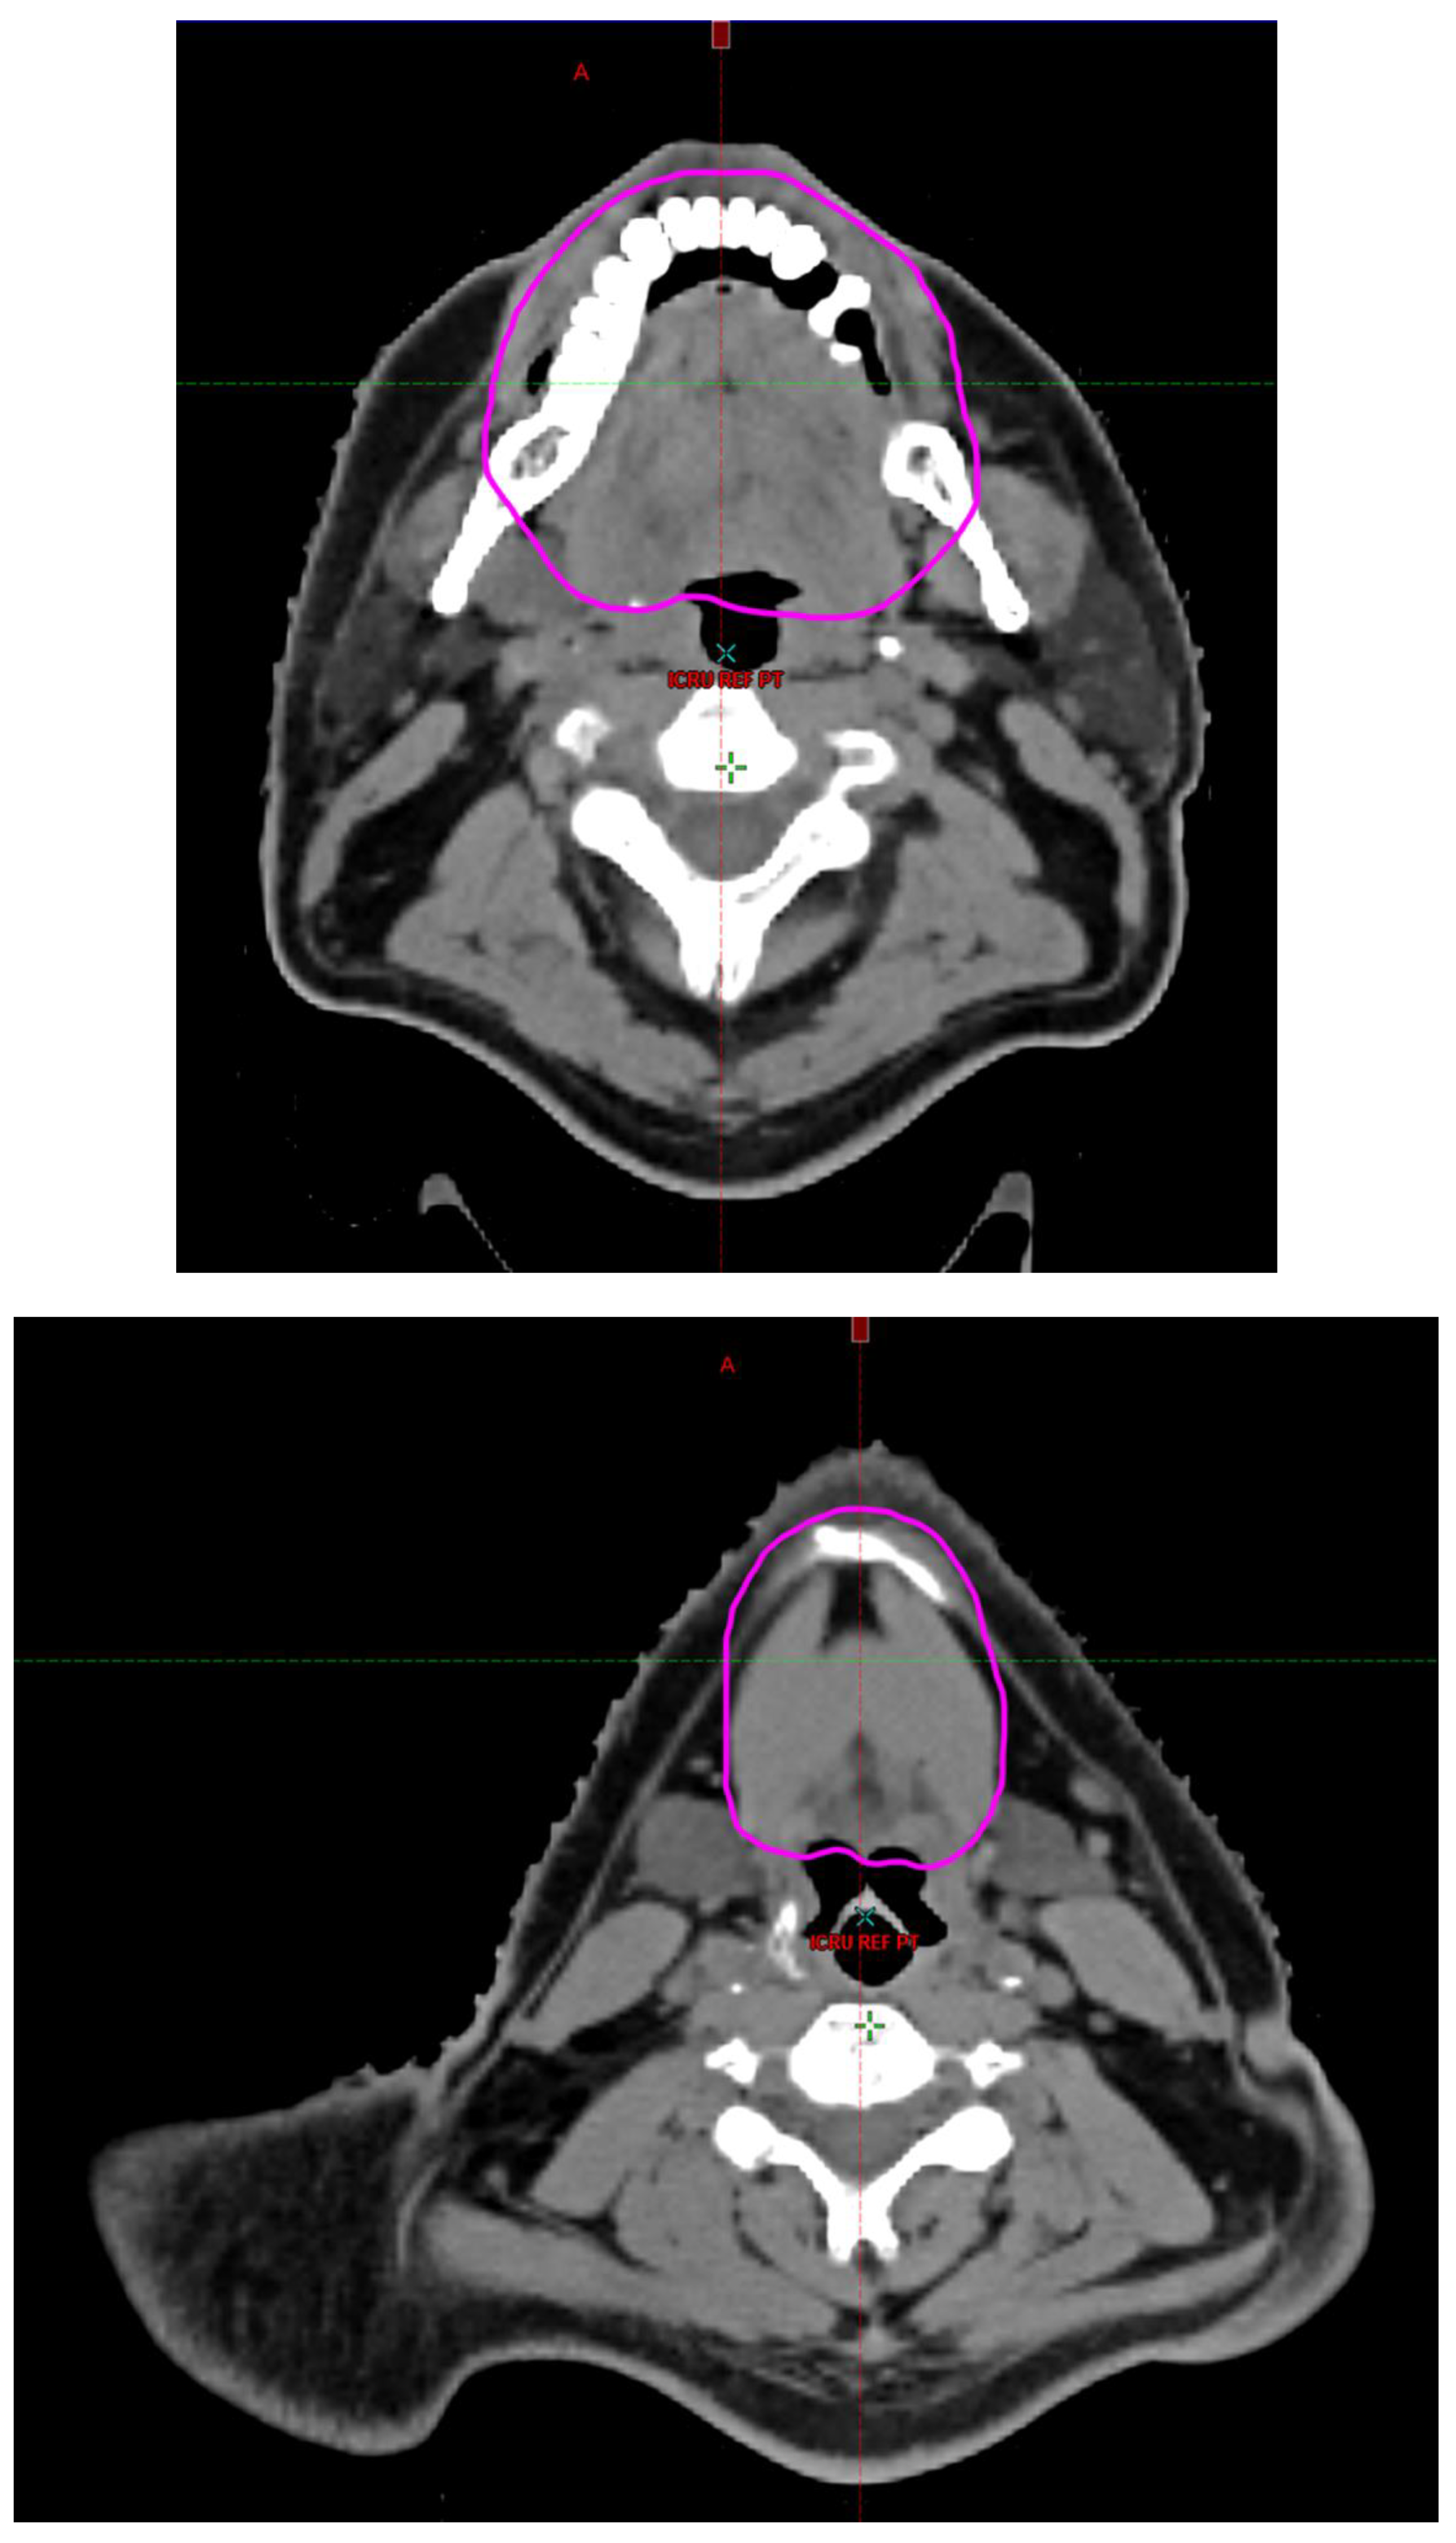

Radiotherapy treatment plans were created, and dose volume histograms (DVH) were generated using the Eclipse treatment planning system (Varian Medical Systems, Palo Alto, CA). The standard photon treatment plans consisted of three volumetric modulated arc therapy fields. The standard proton treatment plans consisted of three to four fields with the pencil beam scanning technique. For proton therapy plans, the RT dose was scaled by 1.1 to account for the difference in relative biological effect when compared to conventional photon treatments. A definition for oral cavity OAR avoidance structure evolved at our institution between 2003 and 2016 when it was formalized and accepted as the consensus standard for treatment planning (Figure 2). The DVH statistics for the oral cavity OAR, and the mean dose to the left and right submandibular glands, left and right parotid glands and total parotid glands were calculated and extracted. Pharyngeal constrictor, intrinsic and extrinsic muscles of the tongue, and laryngeal DVH statistics were not included since swallowing function is not a primary endpoint for this study. There were four patients who did not complete the planned course of treatment. In these cases, the prescribed dose was scaled to the delivered dose.

The superior extent of the oral cavity OAR avoidance structure includes all the mucosa of the hard palate. The contouring of the OAR begins superiorly at the first sign of mucosa on the alveolar ridge of the maxilla (medial and lateral) and hard palate. It then continues inferiorly to include the mucosa of the upper and lower lip, mucosa of the hard and soft palate including the uvula, the buccal mucosa including the buccinator muscles, the mucosa of the retromolar trigone, the entire tongue (anterior two-thirds, dorsal surface and tongue base), floor of mouth, sublingual glands, gingival mucosa of the mandible (lingual and buccal surfaces), and ending at the level of the cranial edge of the hyoid bone and caudal edge of the mandible. It also includes the maxillary and mandibular teeth if present. The posterior extent includes the soft palate, uvula, and tongue base. The anterior extent includes the mucosal surface of the posterior one-half of the lips and the gingival mucosa of the maxillary and mandibular alveolar ridges and retromolar trigone. The lateral extent includes the buccal mucosa and buccinator muscles. The oral cavity OAR contains most of the taste buds which are located within the mucosa of the anterior two-thirds of the tongue, the floor of mouth, the buccal mucosa, the lips, the pharynx (including the soft palate, uvula, and base of tongue), the larynx (epiglottis) and upper third of the esophagus [4]. The oral cavity OAR also contains the minor salivary glands located within buccal, labial, lingual, soft palate, lateral parts of the hard palate, and floor of the mouth submucosa and in the trough circling the circumvallate papillae on the dorsal surface of the tongue near the terminal sulcus [3]. Therefore, the oral cavity OAR for radiotherapy (RT) treatment planning purposes is defined as including the anterior two-thirds of the tongue, floor of mouth, buccal mucosa, mucosal surface of the lips, soft palate, uvula, base of tongue, hard palate and circumvallate papillae on the dorsal surface of the tongue. The gingival mucosa of the alveolar ridges of the mandible and maxilla and the mucosa of the retromolar trigone are also included in the definition to further reduce the incidence and severity of painful oral mucositis. Finally, the sublingual glands are included in the oral cavity OAR structure. The larynx (epiglottis) and upper third of the esophagus are not included in this OAR volume because they are included in their own OAR avoidance structure (larynx, cricopharyngeal inlet, cervical esophagus).

Figure 2. Oral Cavity Organ at Risk (OAR) Avoidance Structure Definition.

Preprints 93045 g002aPreprints 93045 g002bPreprints 93045 g002cPreprints 93045 g002d